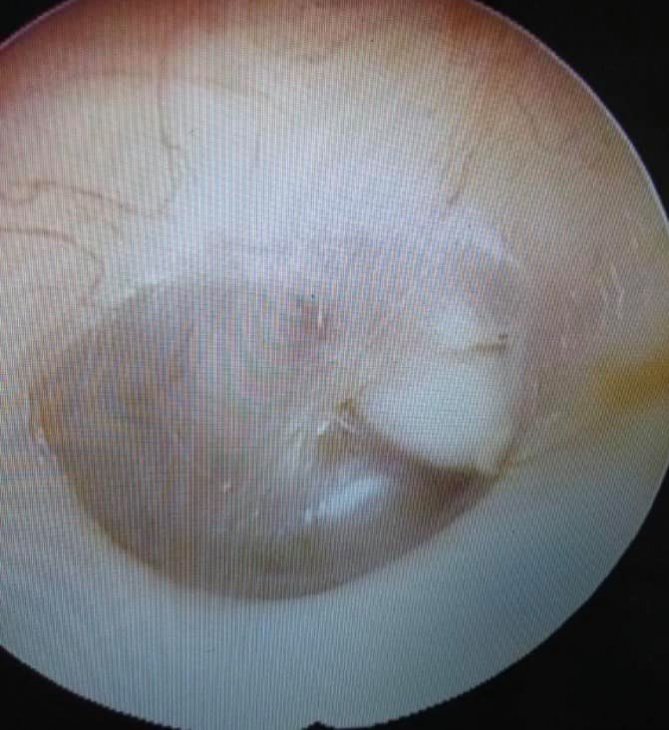

У Львові 4-річному хлопчику видалили пухлину рідкісним способом (ФОТО)

Лікарі Львівської Обласної Дитячої Клінічної Лікарні Охматдит вперше провели операцію малоінвазивним способом (через слуховий хід). Медики видалили пухлину у 4-річного хлопчика без допомоги закордонних колег. Про це повідомили на сторінці медичного закладу.

"Лікарі видалили пухлину у вусі малоінвазивним способом - через слуховии? хід - у 4-річного хлопчика уперше у Львові! Наші дитячі ЛОРи вперше виконали таку операцію самі, без підтримки закордонних колег", - йдеться у дописі.

У дитини діагностували холестеатому - пухлиноподібний утвір вуха. Ця хвороба загрожує життю маленького пацієнта, бо з часом вона росте і може нагноїтися, а гній може потрапити у мозок. А ще це небезпечно для слуху, кажуть лікарі.

"Холестеатому називають пухлиноподібним утвореннням, бо вона складається з клітин шкіри у капсулі. Утворення небезпечне, бо воно росте, а з ним і загроза для дитини. Саме тому важлива рання діагностика. Наші ЛОРи виконали сучасне малоінвазивне мікрохірургічне втручання, яке є золотим стандартом в усьому світі - видалення холестеатоми через слуховий хід. Розміри пухлини це дозволяли".

Львівські медики кажуть, що досвід з проведення таких операцій переймали у закордонних колег з Польщі, США, Австрії, Бельгії.